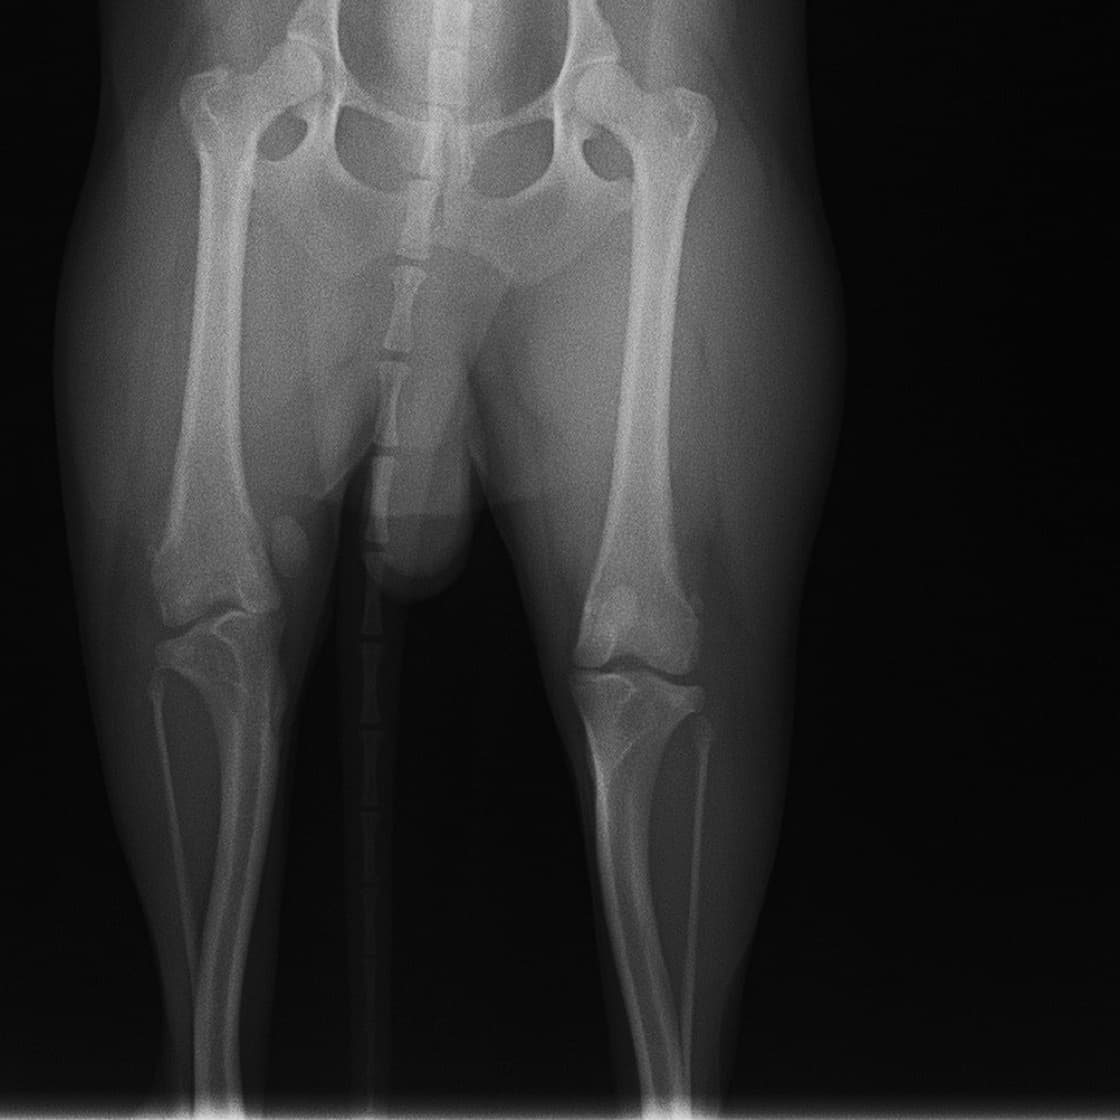

■ 症例22 ポメラニアン 1歳5か月 去勢雄

左後肢の挙上を主訴に来院した。整形学的検査、レントゲン検査より左右の膝蓋骨脱臼(左GradeⅡ〜Ⅲ、右Grade Ⅱ)を認めた。また、脛骨の前方引き出し試験の際に、引き出し兆候は認められないものの、疼痛が認められたため、前十字靭帯の損傷が疑われた。術中における、目視および関節内の操作によって、前十字靭帯の損傷や過伸展といった異常が認められなかったため、膝蓋骨脱臼の整復のみ実施した。手術手技は縫工筋及び内側広筋の解放、脛骨粗面の外側転位、滑車ブロック形造溝術、内外側関節包の縫縮を実施した。本症例は跛行もなく経過良好である。しかし、頸骨高平部の角度(TPA)が 右26.2°、左24.9°であり、解剖学的に前十字靭帯損傷のリスクが高いことから今後の経過に注意が必要である。